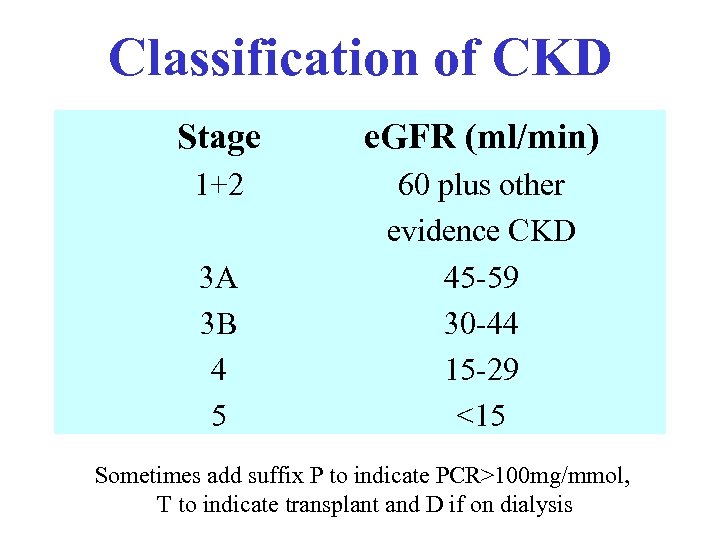

Classification of CKD Stage e. GFR (ml/min) 1+2 60 plus other evidence CKD 45 -59 30 -44 15 -29 <15 3 A 3 B 4 5 Sometimes add suffix P to indicate PCR>100 mg/mmol, T to indicate transplant and D if on dialysis

Classification of CKD Stage e. GFR (ml/min) 1+2 60 plus other evidence CKD 45 -59 30 -44 15 -29 <15 3 A 3 B 4 5 Sometimes add suffix P to indicate PCR>100 mg/mmol, T to indicate transplant and D if on dialysis